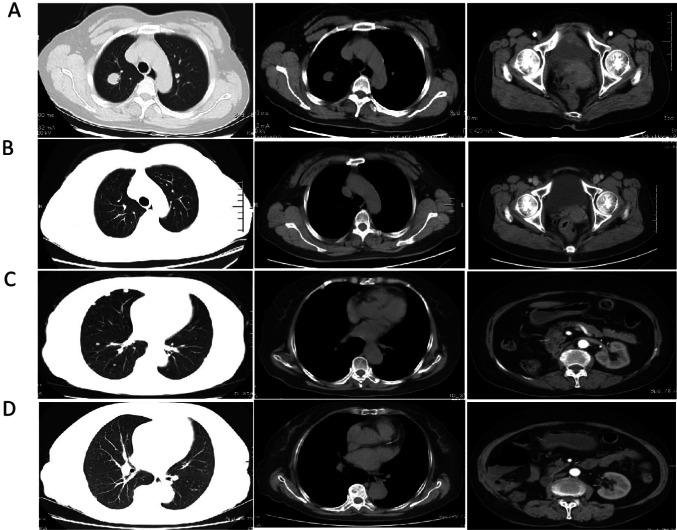

https://cdn.ncbi.nlm.nih.gov/pmc/blobs/e967/12008086/71322a1cd63c/12672_2025_2362_Fig4_HTML.jpg

https://cdn.ncbi.nlm.nih.gov/pmc/blobs/e967/12008086/ead25b4731fb/12672_2025_2362_Fig1_HTML.jpg

https://cdn.ncbi.nlm.nih.gov/pmc/blobs/e967/12008086/87a2fd4c2198/12672_2025_2362_Fig2_HTML.jpg

https://cdn.ncbi.nlm.nih.gov/pmc/blobs/e967/12008086/dabcb7107a80/12672_2025_2362_Fig3_HTML.jpg